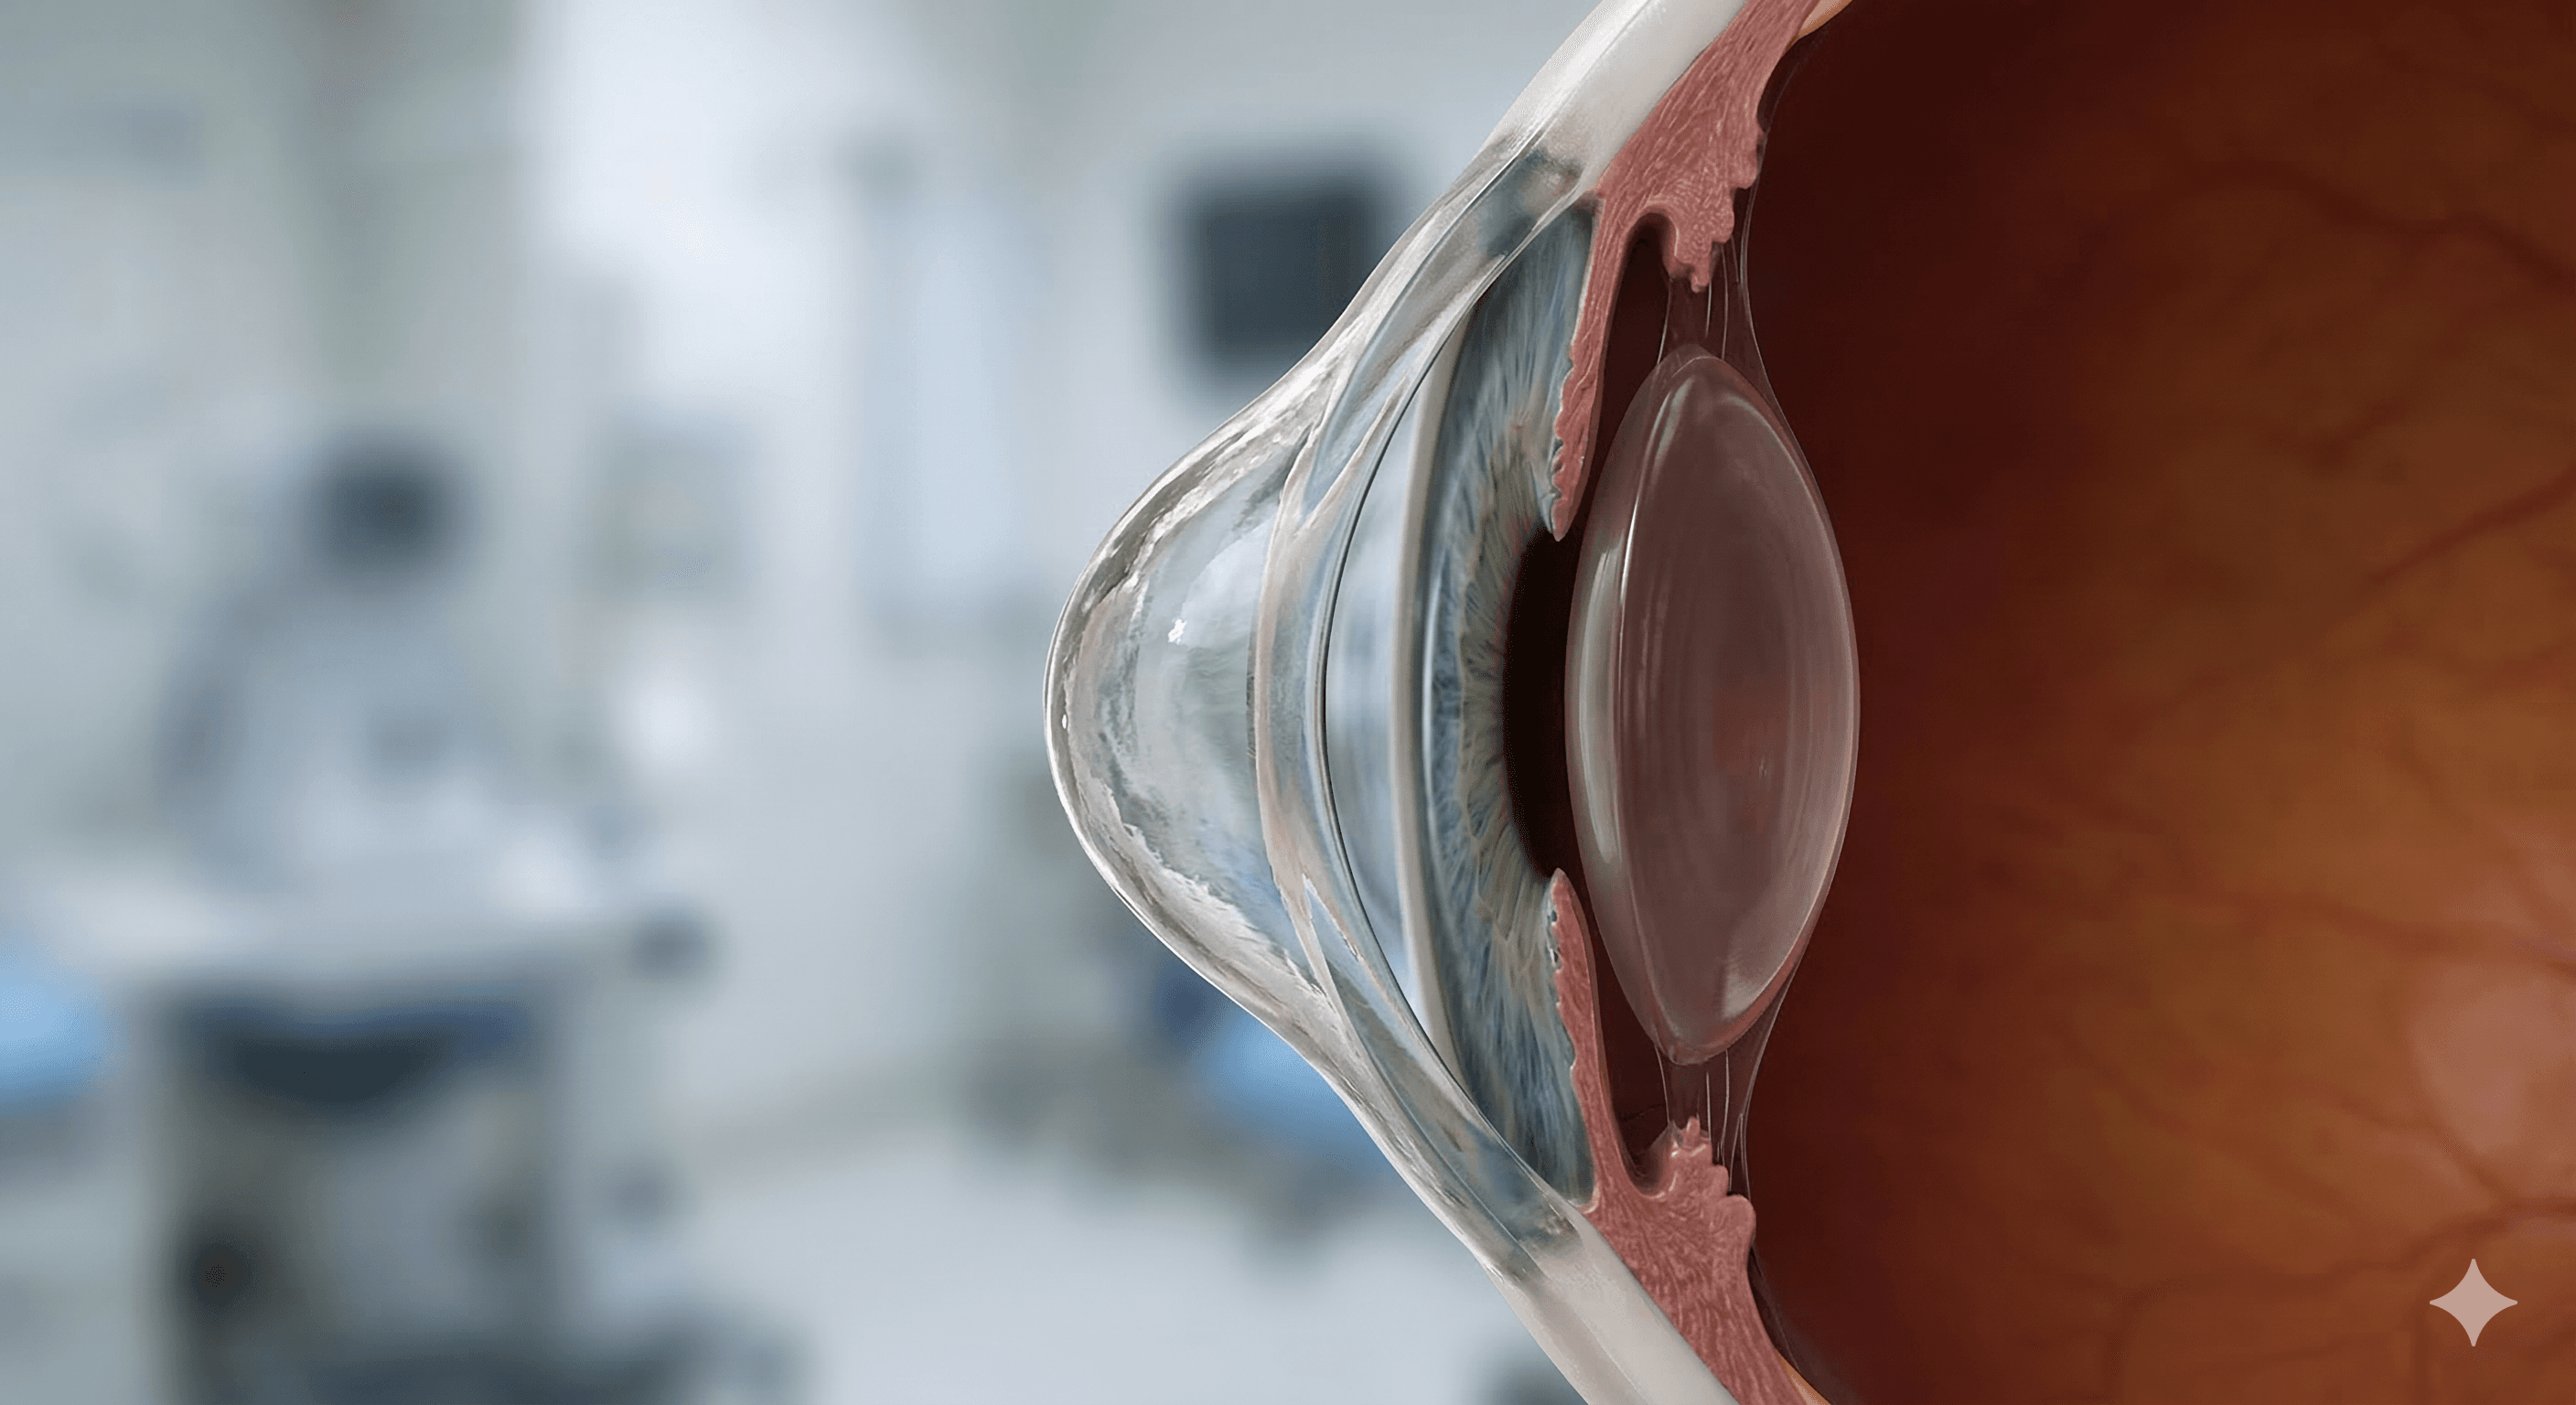

Cirugía de Catarata

LASIK y Cirugía Refractiva

Trasplante de Córnea

Microcirugía Ocular

Córnea y cirugía refractiva y microcirugía de segmento anterior del ojo

Queratocono

El queratocono es una afección progresiva en la que la córnea se adelgaza y comienza a abultarse en forma de cono, lo que provoca una visión distorsionada.

Degeneración marginal pelúcida

Es un trastorno corneal ectásico poco común, caracterizado por un adelgazamiento periférico en la zona inferior de la córnea que genera un astigmatismo irregular.

Ectasia post lasik

Complicación postoperatoria donde la córnea se vuelve inestable y se abulta hacia adelante tras una cirugía láser, similar a un queratocono inducido.